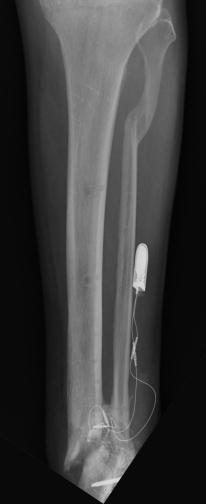

8 Months(+) After Amputation (Prosthesis)

Putting a little time between the amputation and Liam's acclimation to the prosthetic, these images are of the most recent x-rays of Liam's

left leg, which looks great and is able to support full body weight. Liam's is almost off all of the drugs and able control the residual pain. As can

be seen in the x-rays, Dr Ott did a great job with providing Liam with a load barring bone structure. The images of Liam's 2 prosthetic legs provide

an idea of what the legs are used for and their capabilities.